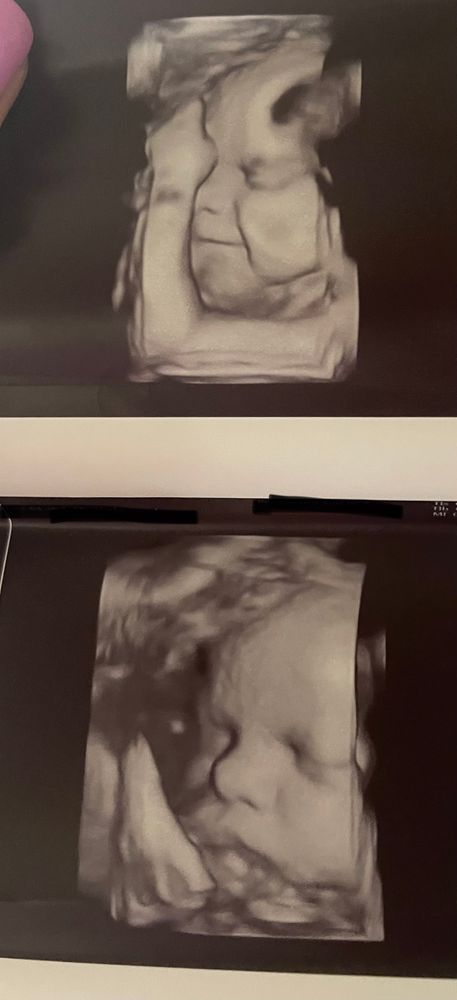

3d узи на поздних сроках)

я тут была на узи в 36 недель и врач-узист сказала цитирую «СД видно на узи на последних неделях, что вы переживаете» «ваша не похожа»

я прям вглядываюсь в свои фотокарточки) а как думаете вы?)

На хорошем аппарате и правда видны некоторые признаки: разрез и посадка глаз, нос шире рта. У вас ничего этого нет)